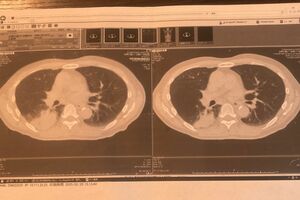

紹介状を手に、大病院の門を叩く。精密検査の結果、右の腎臓と右の肺にそれぞれ異なるがんが確認された。

「転移かと思ったら、2か所に全然違うがんが同時発生していたそうです。そんなことあるんですかと先生に聞いたら、珍しいけど特異なことではないと言っていましたね。転移の場合はステージ4だったけど、別々のがんということで、ステージ3の診断になって。腎臓と肺、個別に治療することになりました」